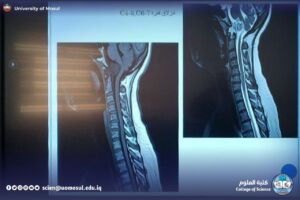

MRI: تبسيط مبدأ T1 وT2، وفهم التباين العالي للأنسجة، وأهم استخداماته في الدماغ والعمود الفقري.